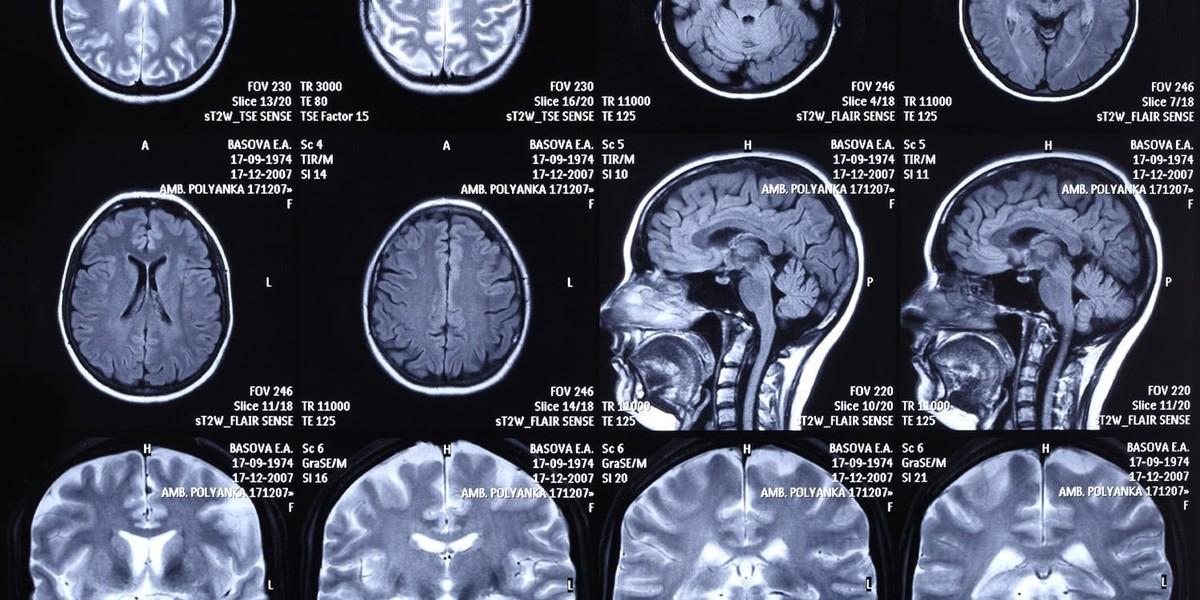

شرکت کنندگان در دستگاه تصویربرداری تشدید مغناطیسی عملکردی (fMRI) قرار گرفتن. این دستگاه از میدان های مغناطیسی قوی برای ردیابی جریان خون در مغز در لحظه استفاده می کنه. وقتی یک ناحیه خاص از مغز سخت تر کار می کنه، به اکسیژن بیشتری نیاز داره و اسکنر این تغییرات ظریف در اکسیژن رسانی خون رو برای نقشه برداری از فعالیت های عصبی تشخیص می ده.

اسکن های مغزی تصویر کاملا متفاوتی رو ارائه دادن. فرآیندهای فکری که باعث این انتخاب های غذایی یکسان می شدن، بسته به هویت سیاسی خریدار، بر نواحی متمایزی از مغز متکی بودن. محققان یک تجزیه و تحلیل کل مغز انجام دادن تا دقیقا محل وقوع این تفاوت ها رو شناسایی کنن.

در میان شرکت کنندگان جمهوری خواه، اسکن های مغزی افزایش فعالیت در اینسولای چپ رو در طول انتخاب های ترکیبی شیر نشون داد. اینسولا منطقه ایه که اغلب در تفسیر حس های درونی بدن و اختصاص دادن ارزش ذهنی به یک کالا نقش داره. جمهوری خواهان همچنین موقع نگاه کردن به روش های تولید شیر، فعالیت بیشتری در قشر پیش پیشانی شکمی-میانی نشون دادن، منطقه ای که با خودشناسی و ارزیابی انتخاب های اقتصادی مرتبطه.

در میان شرکت کنندگان دموکرات، اسکن های مغزی افزایش فعالیت در پره کونیوس راست و شکنج پیشانی فوقانی راست رو در طول انتخاب های ترکیبی تخم مرغ نشون داد. پره کونیوس اغلب با یادآوری خاطرات شخصی و پردازش اطلاعات اجتماعی در ارتباطه. شکنج پیشانی فوقانی هم مثل دروازه ای برای هدایت توجه و مدیریت منابع شناختی عمل می کنه.

محققان این الگوهای فعال سازی مغز رو گرفتن و وارد مدل های آماری کردن. اونا می خواستن ببینن آیا داده های عصبی به تنهایی می تونن به درستی یک شرکت کننده رو به عنوان جمهوری خواه یا دموکرات طبقه بندی کنن یا نه. مدل ها فوق العاده خوب عمل کردن و بین 76 تا 94 درصد مواقع، حزب سیاسی فرد رو درست حدس زدن.

در یک مدل خاص که کاملا بر اساس فعالیت مغزی در طول انتخاب های ترکیبی تخم مرغ بود، سیستم 100 درصد مواقع شرکت کنندگان دموکرات رو به درستی شناسایی کرد. این نرخ های طبقه بندی در مقایسه با حدس تصادفی بسیار دقیق هستن. اونا همچنین از روش های پیش بینی سنتی که صرفا بر اساس میزان محافظه کار بودن والدین فرد هستن، بهتر عمل می کنن.